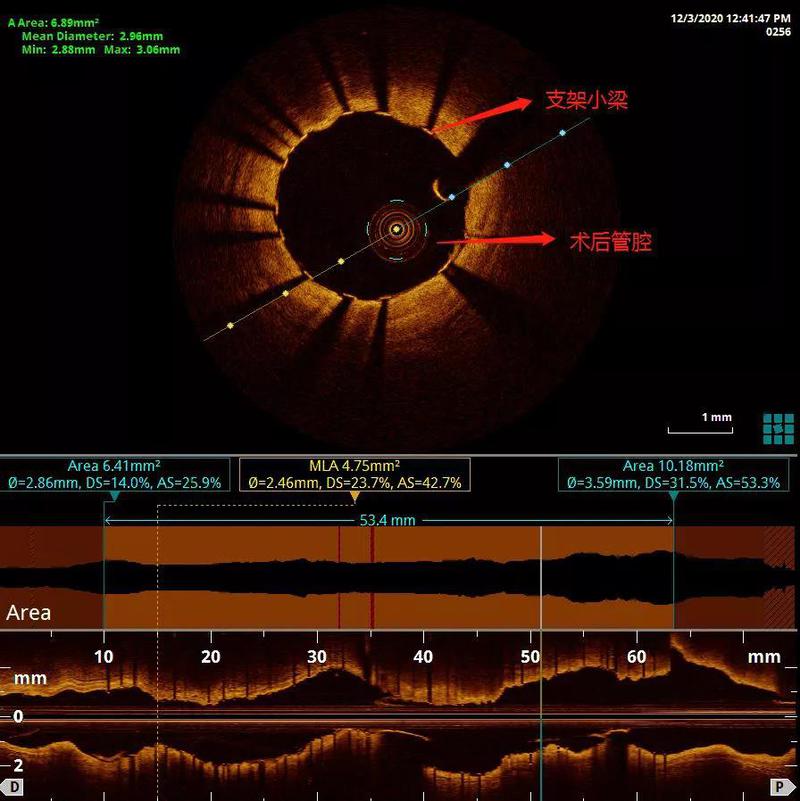

经过OCT检查,评估最小管腔面积约1.13mm2,斑块性质以纤维脂质成分为主,同时,狭窄部位内膜不连续、并可见少量附壁血栓,经充分预扩张处理后,在OCT指引下精准植入药物洗脱支架2.75×29mm,3.0×23mm两枚,随后2.75及3.0球囊后扩张后OCT评价,近端有大于400μm连续不贴壁,再次用3.5球囊20atm扩张后支架完全贴壁,术后最小支架面积达4.75mm2,未见支架远近端夹层,贴壁良好,支架膨胀率大于90%,达到理想效果。

患者PCI术后,支架膨胀,贴壁良好